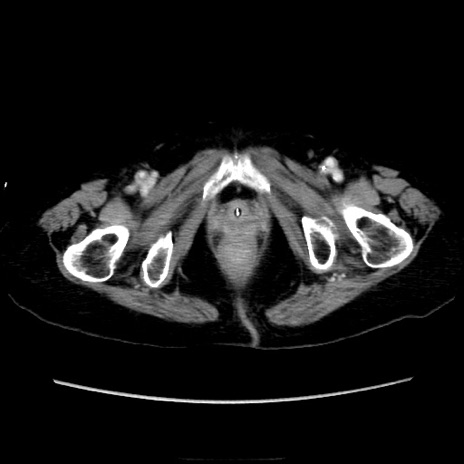

症例40(横断像)

横断像